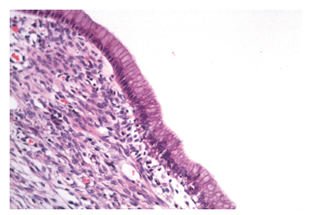

Se extrajo una lesión quística de 12 x 8 x 8 cm compuesta de un material lechoso y una lesión polipoide de 3 cm en su interior. Microscópicamente, la pared del quiste está revestida por células epiteliales columnares con citoplasma de aspecto mucinoso y núcleos sin atipia significativa que se rodean de un estroma de aspecto ovárico (Figura 4). Los ganglios linfáticos regionales y los bordes de resección pancreáticos no estaban comprometidos por el tumor. Los estudios de inmunohistoquímica mostraron reactividad en las células epiteliales para CA 19-9, citoqueratina 7 (Figuras 5 y 6), y reactividad en el estroma subyacente para receptores de progesterona, actina de músculo liso y desmina (Figuras 7, 8 y 9).

Macroscópicamente, las NQM están rodeadas por una pared fibrosa gruesa, en ocasiones calcificada; su contenido es mucinoso o una mezcla de mucina con líquido hemorrágico o acuoso. Microscópicamente, el quiste está recubierto por células epiteliales productoras de mucina que pueden ser planas, columnares o de aspecto papilar, con diferenciación intestinal o gástrica 1. Son positivos para antígeno de membrana epitelial, citoqueratinas 7, 8, 18, 19 y CA 19-9 5. La presencia de estroma similar al ovario es característico y necesario para establecer el diagnóstico de NQM. Las células estromales pueden presentar reactividad para receptores de estrógeno y receptores de progesterona, vimentina, actina de músculo liso, desmina, calretinina, inhibina α, melan-A, tirosina hidroxilasa, CD 99, y célula-B CLL/linfoma 2 (Bcl-2) 1,6.